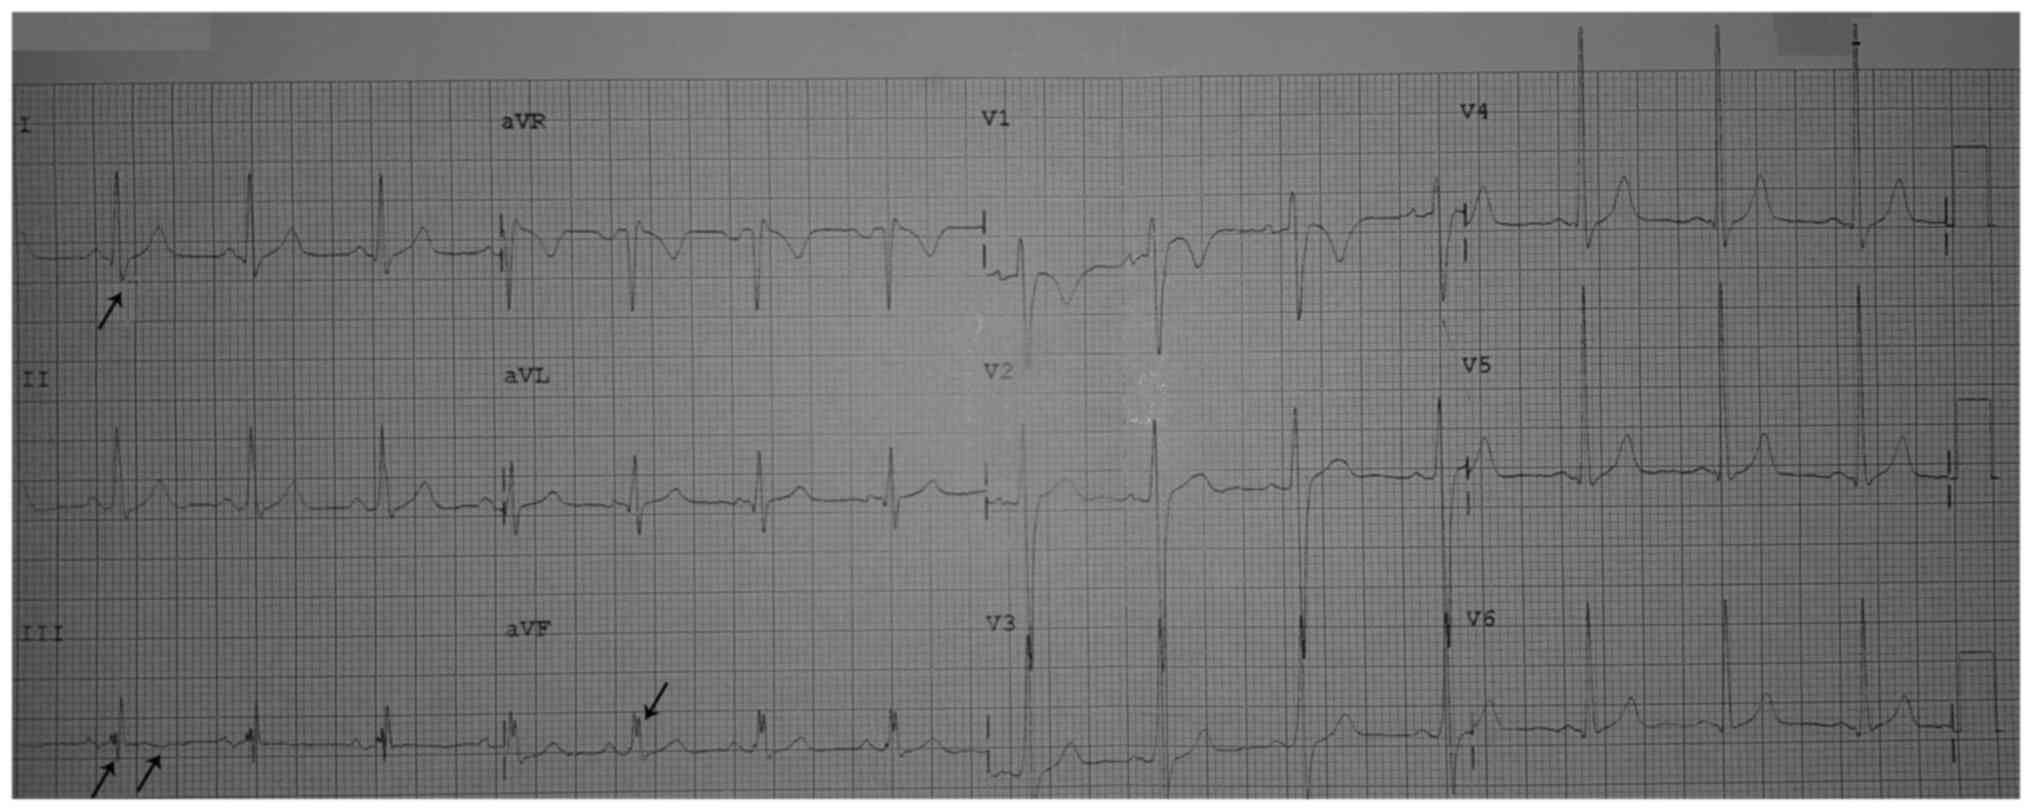

Following admission to the Department of Cardiology, the patient had no fever, was hemodynamically stable, had a normal respiratory rate, had 94% oxygen saturation while breathing ambient air and exhibited barely audible respiratory sounds in his left lung basal segment, as well as fine rales. Routine laboratory tests demonstrated eosinophilia (12.2%; normal cut off, 5%), elevated D-dimer (464 ng/ml; normal cut off, 250 ng/ml) and elevated C-reactive protein (3.9 mg/dl; normal cut off, 0.3 mg/dl) levels. A standard electrocardiogram demonstrated an S1Q3T3 pattern and nonspecific intraventricular conduction delay in the inferior leads (Fig. 2). Furthermore, transthoracic echocardiography (TTE) revealed a slightly enlarged right ventricle (RV), with moderate RV systolic dysfunction, as well as a bi-lobular mass attached to the right ventricular free wall adjacent to the right ventricular inflow, without causing any inflow obstruction (Fig. 3A). Transesophageal echocardiography did not provide any additional information. Furthermore, at that time, the patient had no other organ involvement. During hospitalization, the patient received low molecular weight heparin (enoxaparin, 60 mg/0.6 ml twice-daily by subcutaneous injection) and a parasitology exam was requested. The ELISA assay (SERION ELISA Classic; SERION Diagnostics) was positive for E. granulosus IgG antibodies (10.18 U/ml; normal cut off, 1.1 U/ml) and therefore antiparasitic treatment using albendazole (400 mg, twice daily) was administered. During hospitalization, the clinical evolution improved and the patient became stable and asymptomatic. The patient was discharged with conservative treatment (albendazole, 400 mg twice-daily; levocetirizine, 5 mg twice-daily) and a recommendation for cardiac surgery evaluation, which the patient refused. In the first year of clinical evolution, the patient was assessed in the Department of Cardiology twice and was stable and asymptomatic. Serial transthoracic echocardiograms demonstrated a marked reduction in the dimensions of the RV cardiac cyst and an increase in its echogenicity (Fig. 3B).

Figure 2

Standard electrocardiogram presenting (on the initial presentation) normal sinus rhythm, normal QRS axis (at 50˚), QRSD 120 msec, ventricular rate 80/min, S1Q3T3 pattern (arrows) and nonspecific intraventricular conduction delay in DIII, and aVF, QTc 404 msec. QTc, corrected QT interval; QRSD, QRS duration; aVR, augmented right vector; aVL, augmented left vector; aVF, augmented vector foot.